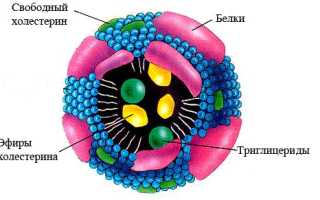

- Липопротеины — основная форма транспортировки липидов в организме. Поскольку липиды не растворимы в воде, они не могут выполнять свои функции самостоятельно. В крови липиды связываются с белками, называемыми апопротеинами, что делает их растворимыми и образует новое соединение — липопротеид или липопротеин. Эти термины взаимозаменяемы и часто сокращаются до ЛП.

Липопротеины играют ключевую роль в транспортировке и обмене липидов. Хиломикроны переносят жиры, поступающие с пищей, ЛПОНП обеспечивают доставку эндогенных триглицеридов к местам утилизации, ЛПНП способствуют поступлению холестерина в клетки, а ЛПВП защищают от атеросклероза.

Липопротеины плазмы крови классифицируются по плотности, что определяется методом ультрацентрифугирования. Чем больше липидов в молекуле липопротеина, тем ниже его плотность. Выделяют несколько типов: ЛПОНП, ЛПНП, ЛПВП и хиломикроны. Эта классификация считается наиболее точной и разработана с использованием высокоточного метода ультрацентрифугирования.

Липопротеины также различаются по размерам. Наибольшими являются молекулы хиломикронов, затем идут ЛПОНП, ЛПСП, ЛПНП и ЛПВП, уменьшаясь по размеру.

Эти липопротеины являются крупнейшими после хиломикронов. Более 50% их состава составляют триглицериды, а также в них содержится небольшое количество холестерина. При повышенном уровне ЛПОНП в крови она может стать мутной и приобрести молочный оттенок.